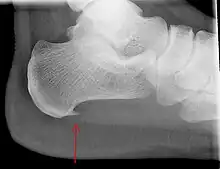

Heel bone with heel spur (red arrow)

An incidental finding associated with this condition is a heel spur, a small bony calcification on the calcaneus (heel bone), which can be found in up to 50% of those with plantar fasciitis.[6] In such cases, it is the underlying plantar fasciitis that produces the heel pain, and not the spur itself.[13] The condition is responsible for the creation of the spur though the clinical significance of heel spurs in plantar fasciitis remains unclear.[12]

Medical imaging is not routinely needed. It is expensive and does not typically change how plantar fasciitis is managed.[15] When the diagnosis is not clinically apparent, lateral view X-rays of the ankle are the recommended imaging modality to assess for other causes of heel pain, such as stress fractures or bone spur development.[7]